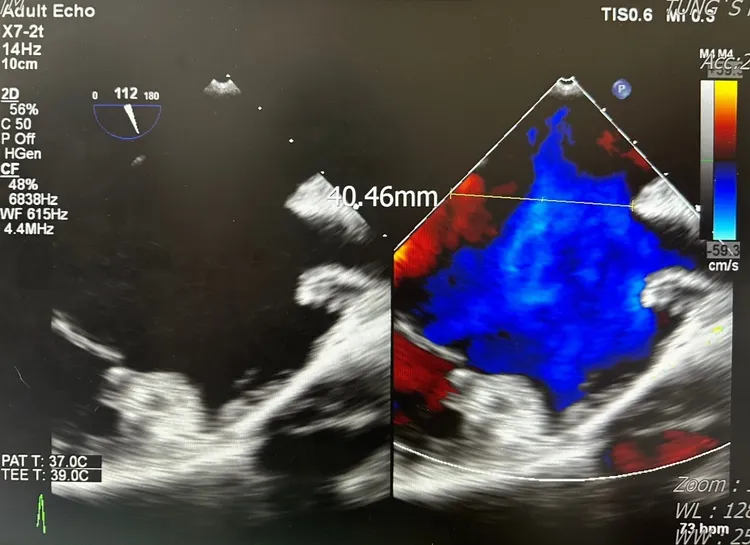

心臟超音波檢查影像發現是先天性心房中隔缺損(缺損直徑已達4公分)。童醫院提供

童綜合醫院表示,黃男一直都熱愛運動,體力也維持得很好,和朋友相邀攀爬號稱「天使的眼淚」的嘉明湖,清晨在山莊出發前溫度驟降,竟然發現體力明顯下降、呼吸困難,連平時看起來很簡單的小階梯跨越,都感覺寸步難行,只好臨時折返,到醫院掛急診,檢查發現是先天性心房中隔缺損,而且缺損直徑已達4公分,還合併右心室擴大及三尖瓣閉鎖不全,醫師建議進行傳統心臟手術。